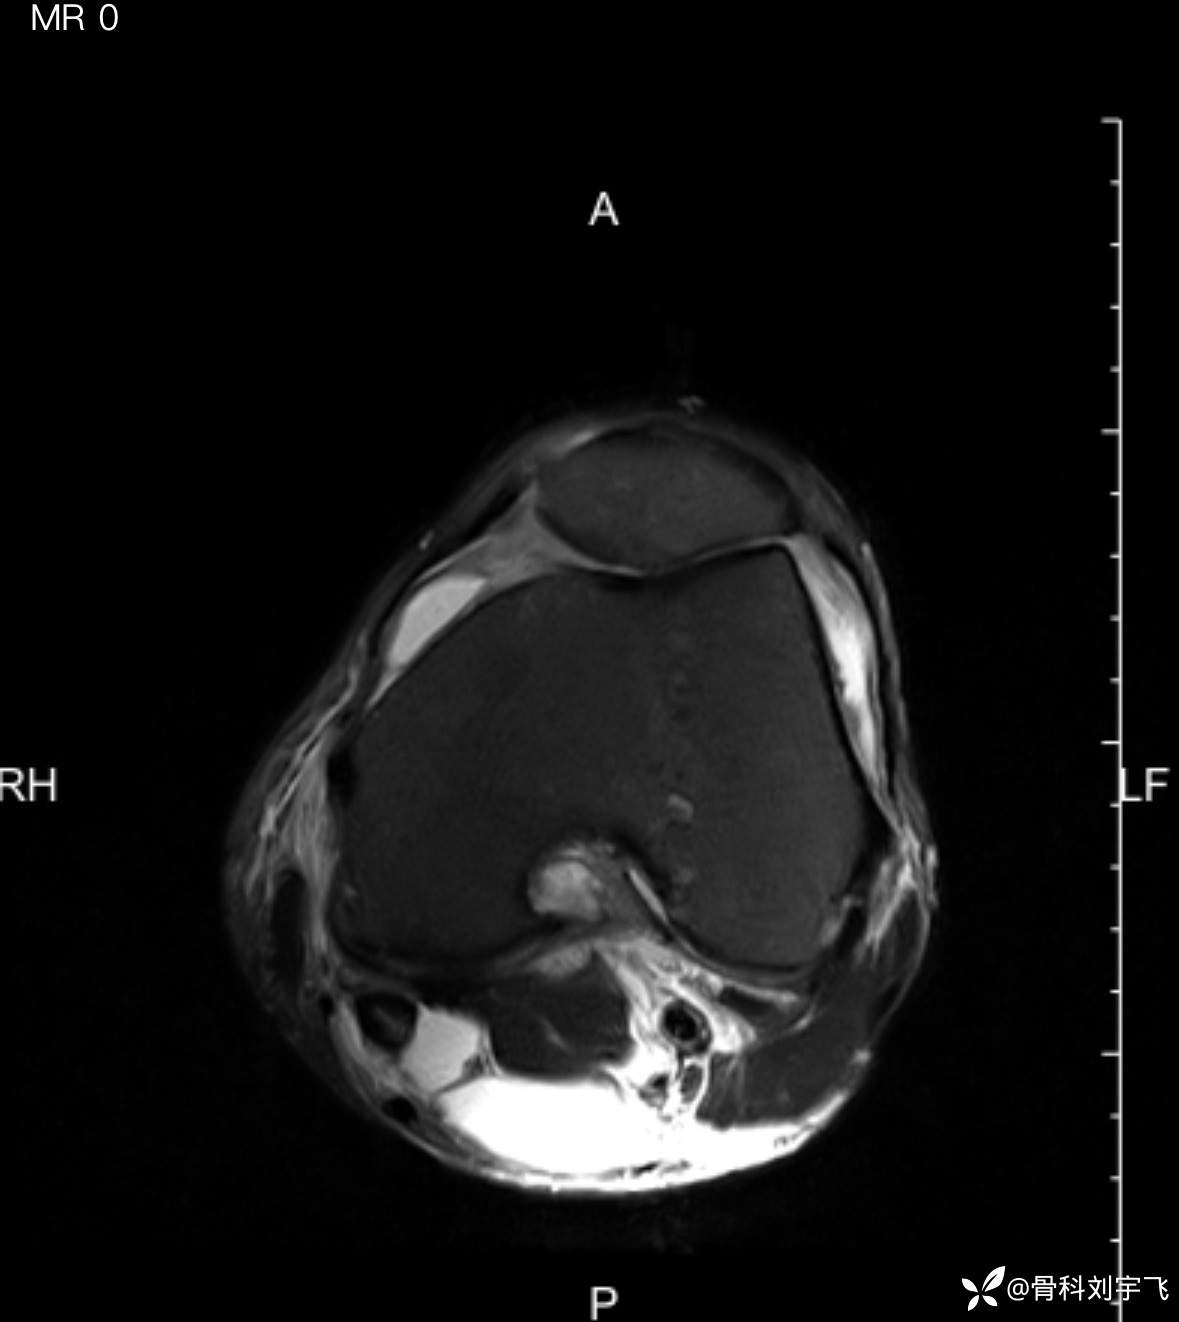

无诱因膝关节疼痛、肿胀做了MRI诊断关节退变、半月板撕裂,最后病因是下肢血栓?

临床诊断:内侧半月板撕裂 肌间软组织水肿?

辅助检查:MRI